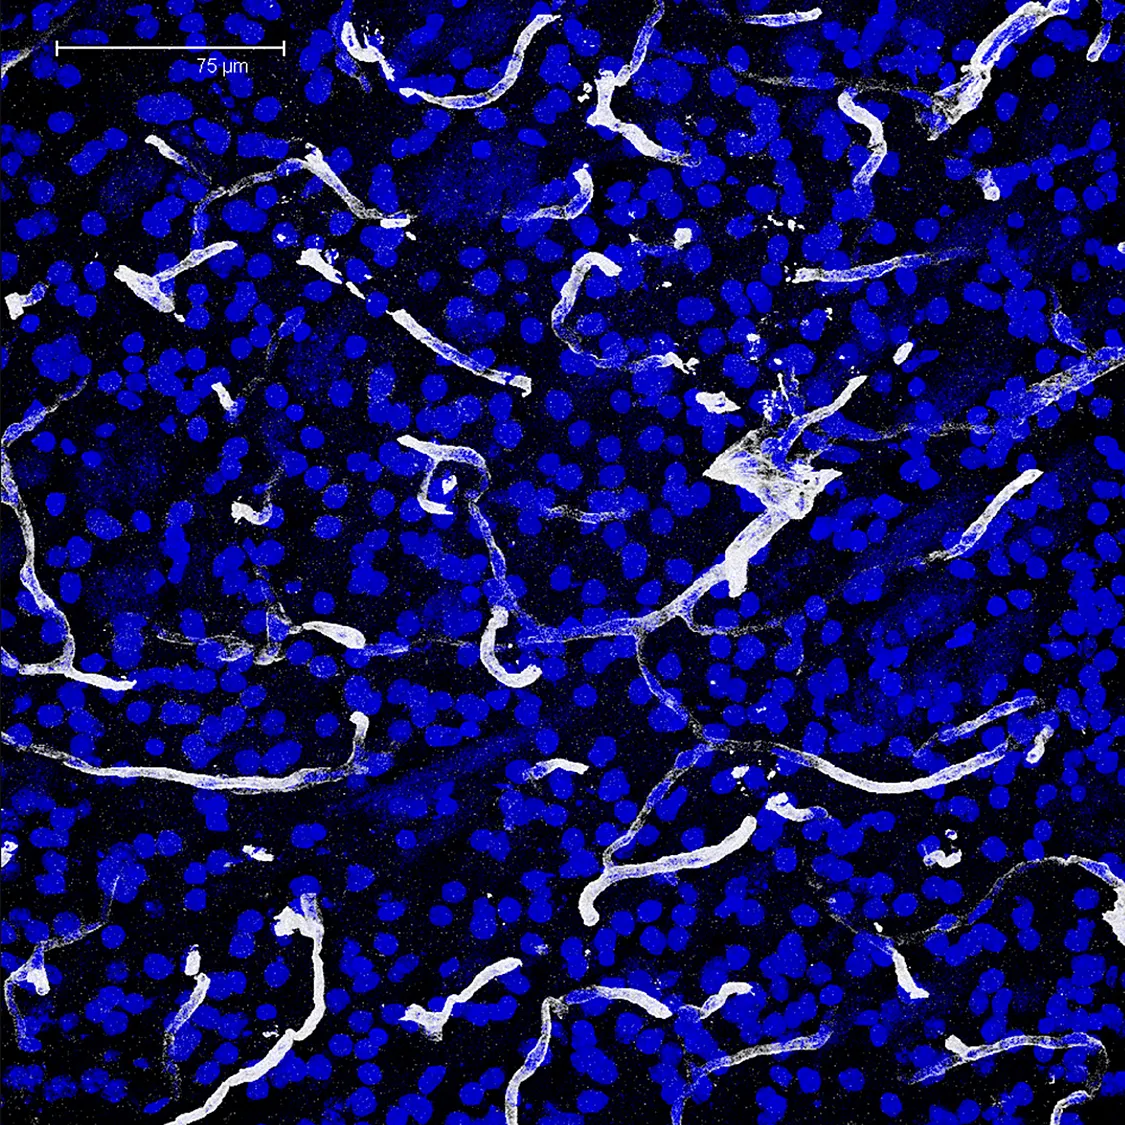

Rat brain, Transparent projection with a threshold of 37.

Nuclei in blue.

Vasculature in gray.

Z depth: 35.41μm